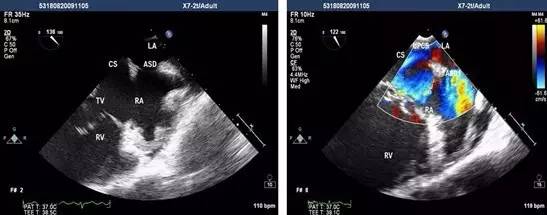

经食管超声心动图是将超声探头置入食管内,从心室的后方向前近距离探查其深部结构,避免了胸壁、肺气等因素的干扰,故可显示出清晰的图像,提高对心血管疾病诊断的敏感性和可靠性。

为什么经食道超声心动图就能发现心房血栓呢?因为食管位于左心房后面,绝大部分人食管与左房后壁都有接触。

通过食管置入超声探头,就能很直观的从左心房后面看到心房里面的结构,能够看清心房、心耳内有无血栓。

而如果使用普通经胸的心室彩超看心房,超声波需要穿过皮肤、肌肉、骨骼、肺等组织,就很难分辨清楚心房内有无血栓。